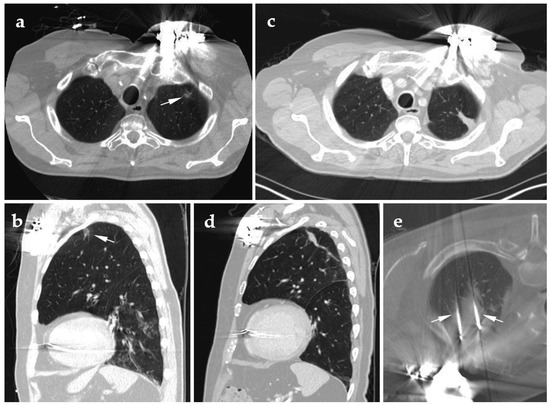

3.4. Pleural Lesions